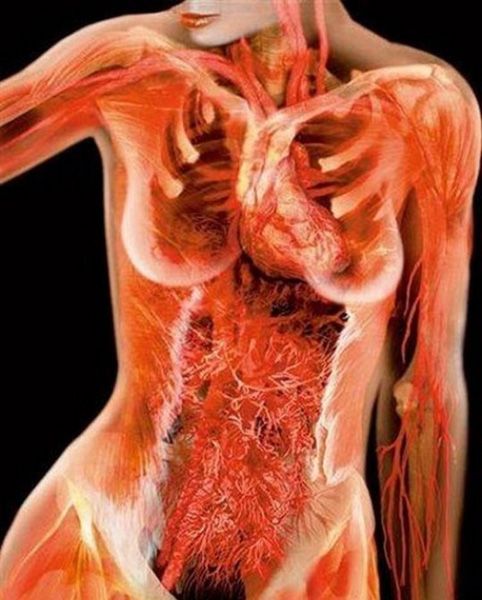

X射线下的人体艺术

生命奥秘:X射线下令人震撼的孕妇和人体艺术